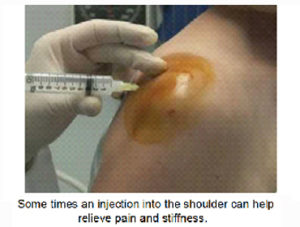

Joint injections:

your surgeon may offer the option of injection into the shoulder joint. They may be sometimes injected under ultrasound guidance. There are many kind of injections, each having different functions. Some injections are intended to reduce pain and inflammation and others to lubricate the joint (viscosupplementation). Please discuss them with your surgeon.